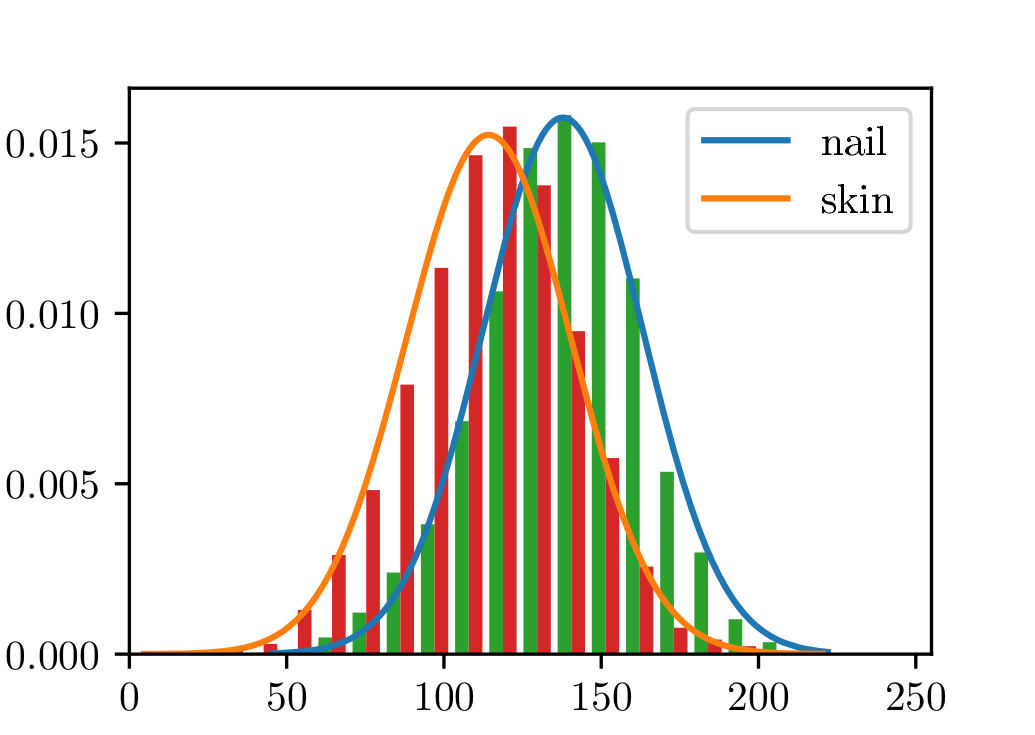

The photometric properties of nail pixels do not contain enough information to segment them from toe ones. In Fig. 1 we group pixels belonging to the nail region and the toe region, respectively. We observe that their distribution across different channels of the CIELAB color space is very similar. In fact, none of the channels, nor a combination of them, has proved to be enough to tell apart these pixels, especially when considering pictures taken under different illumination conditions. Thus, although nail and toe can be easily discriminated by a human observer, doing so based only on pixel-based local information poses as an arduous challenge.

Nail and skin can not be segmented using only color or local information. The pixel-wise colors of human nails are indistinguishable from those belonging to toes (see Sect. 2). This is specially important when dealing with different skin shades or illumination conditions. We can not, however, disregard photometric information (see Fig. 9).